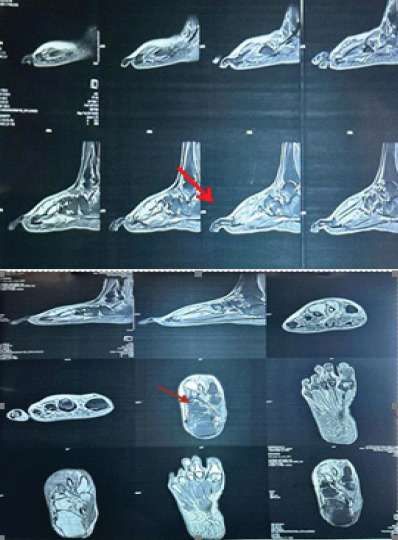

Case report: We present a case of a 65-year-old male farmer who presented with swelling and persistent pain in the right foot, particularly over the third toe. The patient had a history of trivial trauma and previous incision and drainage for a foot swelling. Radiographic and magnetic resonance imaging findings indicated a well-defined lytic lesion with cortical thinning and breach over the third metatarsal, raising suspicion for tuberculous osteomyelitis. Surgical exploration revealed an encapsulated cyst filled with cheesy material. No sequestrated bone or osteomyelitis was found.